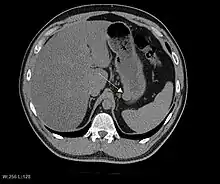

CT image of a GIST in the gastric cardia. The lesion appears submucosal, is hypervascular and protrudes intraluminally. Upper GI bleeding led to endoscopy, finding an ulcerated mass.

Non-enhanced CT image of a small GIST in the posterior stomach wall (arrow). The lesion appears subserosal. Incidental finding.